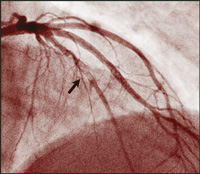

Though there have been similar case reports,17,18 ours is a unique example of an angiographically proven very late stent thrombosis, 3 years after placement of DES. During angiography 9 days prior to the event, no abnormality was noted within the previously implanted DES, nor at the stent edges before the cessation of clopidogrel therapy. Nine days after stopping therapy with this drug, filling defects were seen (Figure, B).